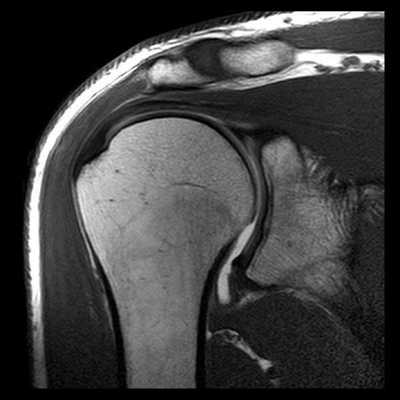

(Слева) МРТ, корональная проекция, режим протонной плотности: признаки ОА, включая полную утрату хряща, субкортикальный склероз и верхние краевые остеофиты. Определяется истончение сухожилия надостной мышцы. На других срезах визуализировались признаки полнослойного разрыва вращательной манжеты. Выпот визуализируется как в плечевом суставе, так и в подакромиально-поддельтовидной сумке.

2. Рентгенография при остеоартрозе плечевого и локтевого суставов:

• Плечевой сустав:

о Нормальная плотность костной ткани

о Субхондральный склероз

о Формирование остеофитов:

- Вокруг суставной впадины лопатки; чаще всего наилучшим образом визуализируются в аксиллярной проекции

- Вокруг анатомической шейки плечевой кости (краевые):

Наибольшее разрастание направлено вниз и кнутри в подмышечный карман

о Субхондральные кисты

о Сужение суставного пространства

о Подвывих в плечевом суставе может формироваться на фоне патологических изменений:

- Верхний подвывих головки плечевой кости на фоне хронического повреждения вращательной манжеты

- Задний подвывих головки при хронической нестабильности (визуализируется при рентгенографии в аксиллярной проекции)

о Внутрисуставные свободные тела:

- Визуализация затруднена, если сустав не растянут выпотом

- Ищите оссифицированные тела в подмышечном и подклювовидном заворотах

У каждого способа обследования имеются свои преимущества и недостатки. На сегодняшний день ведущую роль в визуализации вне- и внутрисуставных структур плечевого сустава играет МРТ, которая позволяет выявлять мягкотканные и костные повреждения в суставах. Она может осуществляться по двум базовым протоколам - бесконтрастная томография и МРТ плечевого сустава с применением парамагнитных контрастных веществ (она же МР артрография). Лидирующую роль в оценке состояния костей плеча играет спиральная компьютерная томография.